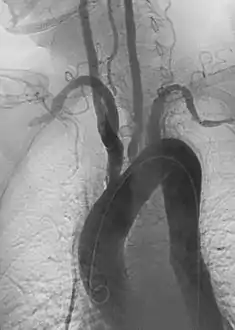

بالرغم من أن أسباب المرض غير معروفة، إلا أن الحالة المرضية تتميز بالالتهاب الحبيبي القطاعي أو الجزئي من الأورطي وفروعه الرئيسية المنبثقة منه. يؤدي هذا الالتهاب إلى ضيق الشرايين، وتجلط الأوردة وتمدد الأوعية الدموية.[3] هناك أيضاً تليف غير منتظم للأوعية الدموية نتيجة التهاب الأوعية الدموية المزمنة مما يؤدي أحياناً إلى تليف البطانة الشريانية (تليف الجزء الداخلي من الأوعية الدموية).[4] ويمكن مشاهدة ضيق واضح نتيجة التهاب الأوعية والأورام الحبيبية وتليف الشرايين في الدراسات الشريانية مثل التصوير بالرنين المغناطيسي (MRA)، وتصوير الأوعية الدموية المبرمج (CTA) أو تصوير الشرايين (DSA).